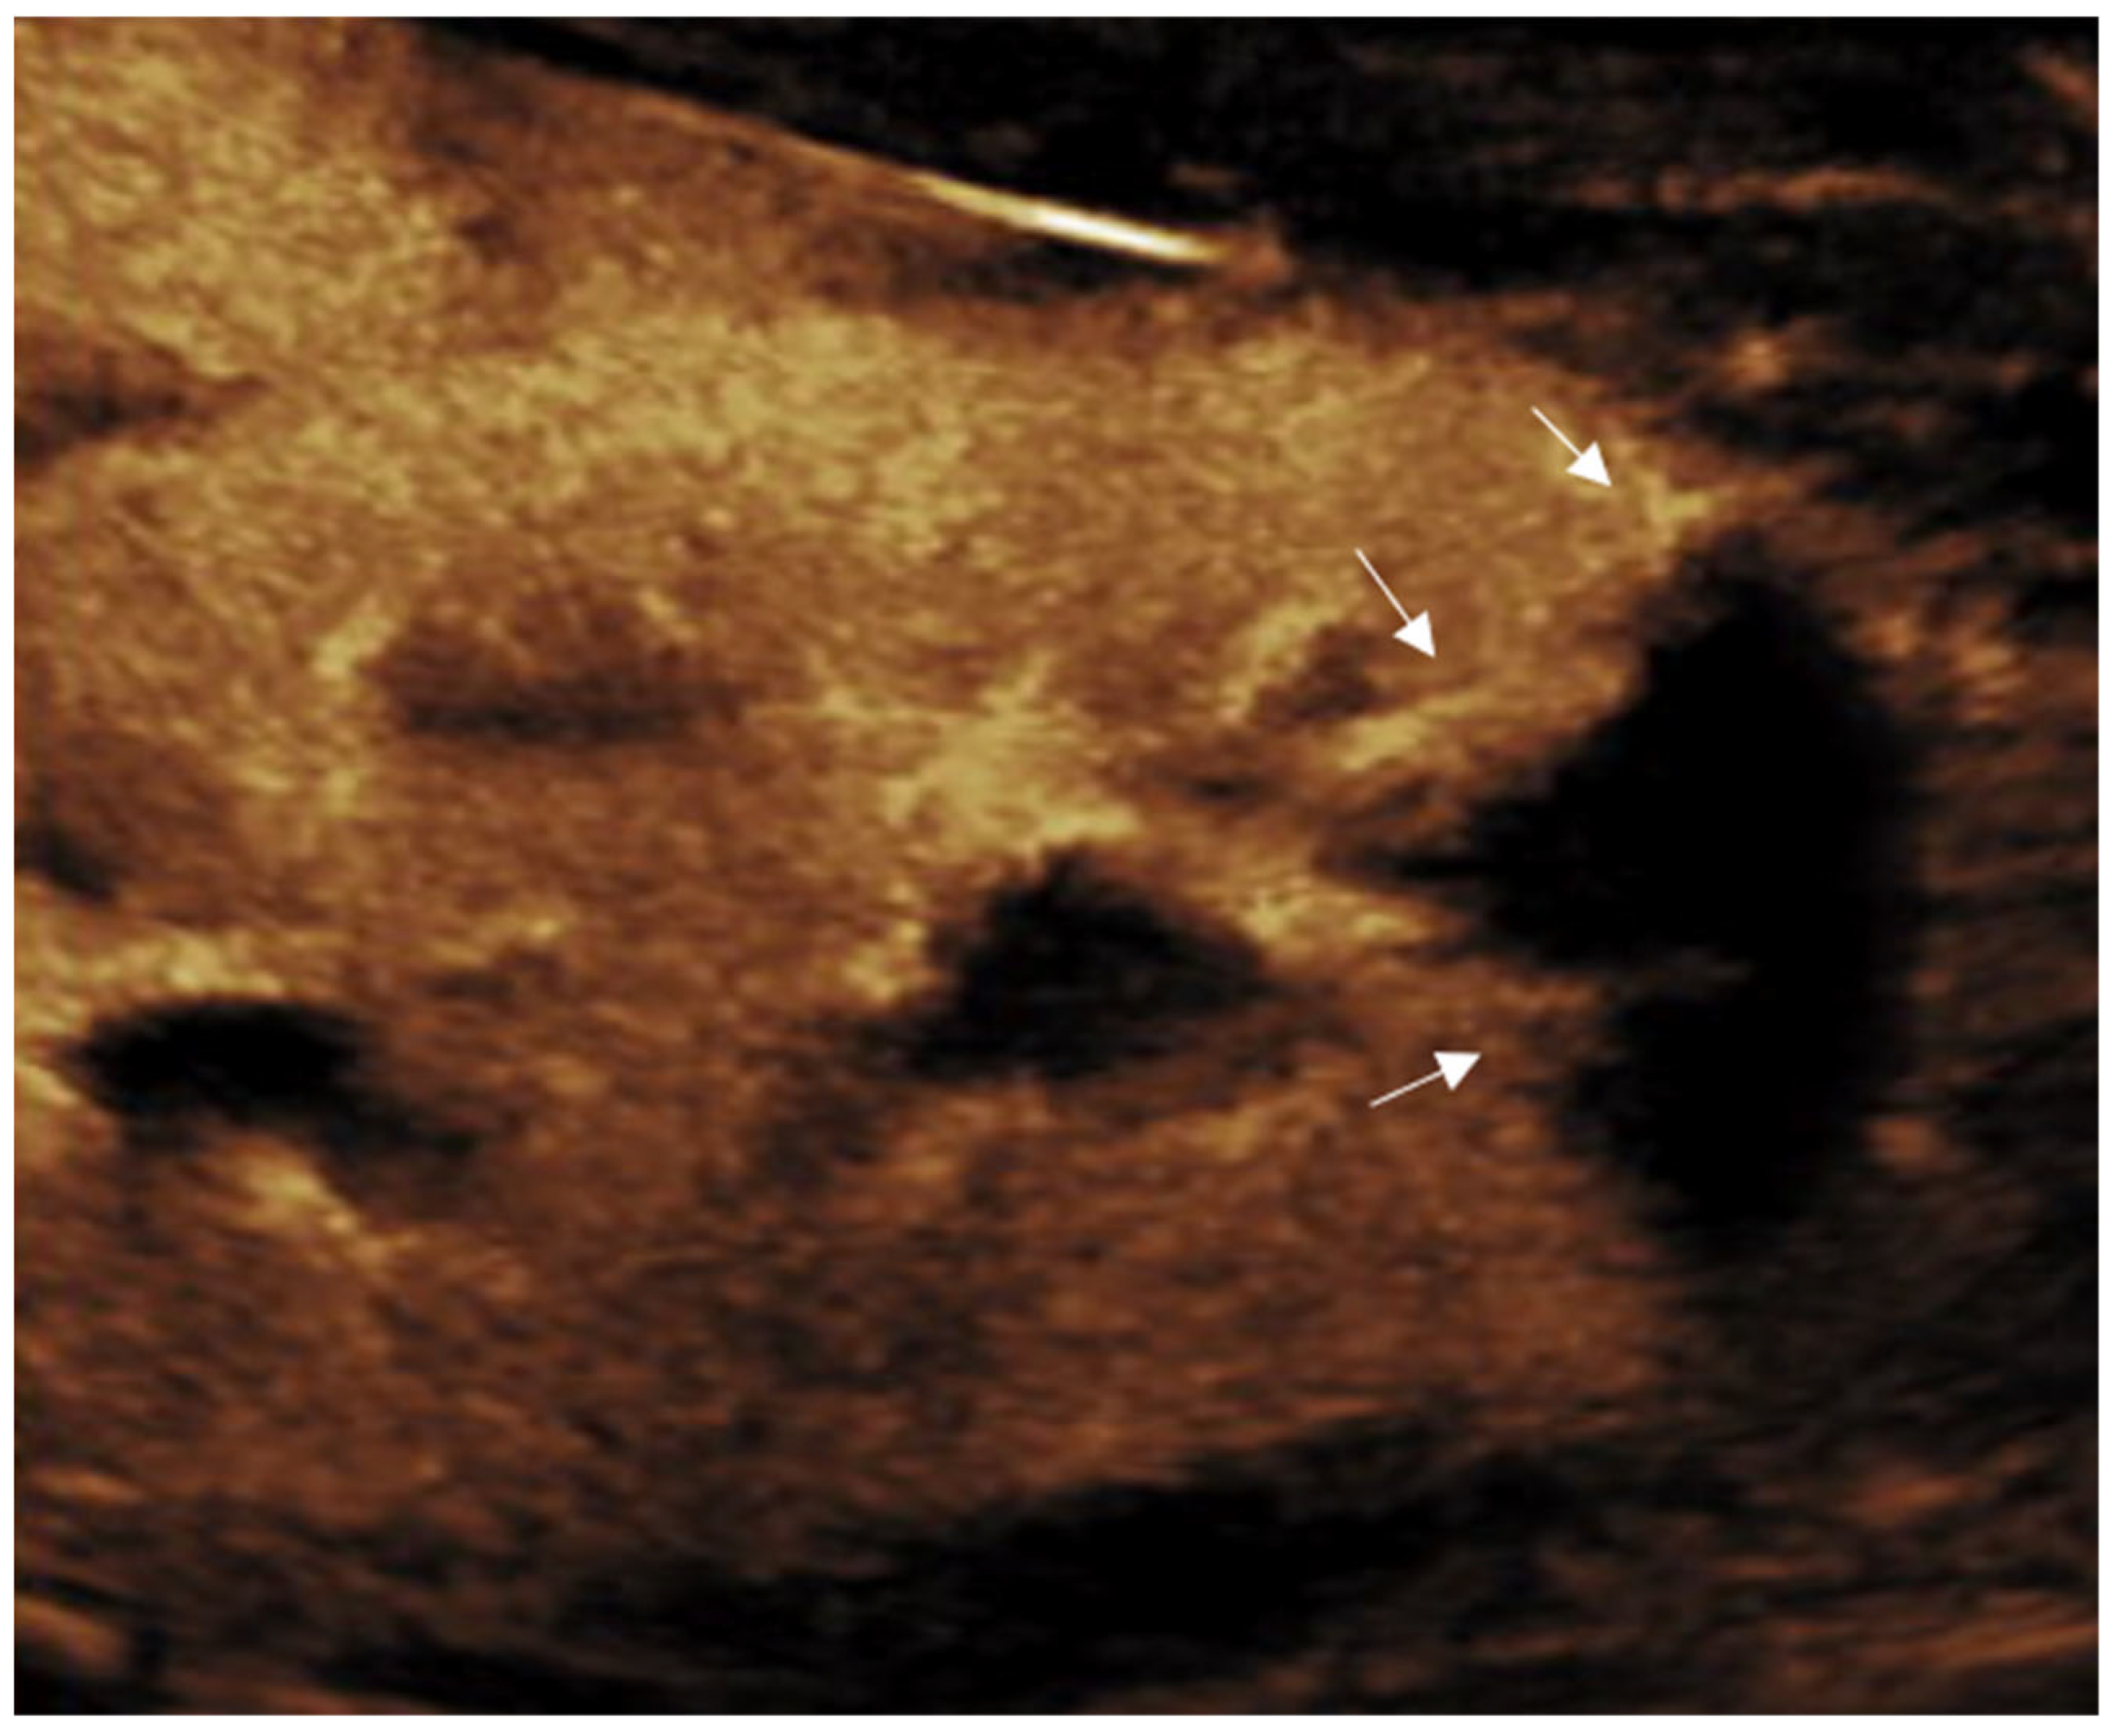

3.3. Kidney

- Pšeničny, E.; Glušič, M.; Pokorn, M.; Ključevšek, D. Contrast-enhanced ultrasound in detection and follow-up of focal renal infections in children. Br. J. Radiol. 2022, 95, 20220290. [Google Scholar] [CrossRef]

- Jung, H.J.; Choi, M.H.; Pai, K.S.; Kim, H.G. Diagnostic performance of contrast-enhanced ultrasound for acute pyelonephritis in children. Sci. Rep. 2020, 10, 10715. [Google Scholar] [CrossRef]

- Rinaldo, C.; Grimaldi, D.; Di Serafino, M.; Iacobellis, F.; Verde, F.; Caruso, M.; Capasso, R.; Esposito, M.; Romeo, V.; Imbriaco, M.; et al. An update on pyelonephritis: Role of contrast-enhanced ultrasound (CEUS). J. Ultrasound 2023, 26, 333–342. [Google Scholar] [CrossRef]

- Kim, B.; Lim, H.K.; Choi, M.H.; Woo, J.Y.; Ryu, J.; Kim, S.; Park, C.M.; Lee, W.J.; Han, M.C.; Song, I.C.; et al. Detection of parenchymal abnormalities in acute pyelonephritis by pulse inversion harmonic imaging with or without microbubble ultrasonographic contrast agent: Correlation with computed tomography. J. Ultrasound Med. 2001, 20, 5–14. [Google Scholar] [CrossRef]

- Boccatonda, A.; Stupia, R.; Serra, C. Ultrasound, contrast-enhanced ultrasound and pyelonephritis: A narrative review. World J. Nephrol. 2024, 13, 98300. [Google Scholar] [CrossRef] [PubMed]

- Basiratnia, M.; Noohi, A.H.; Lotfi, M.; Alavi, M.S. Power Doppler sonographic evaluation of acute childhood pyelonephritis. Pediatr. Nephrol. 2006, 21, 1854–1857. [Google Scholar] [CrossRef] [PubMed]

- Expert Panel on Urologic Imaging; Nikolaidis, P.; Dogra, V.S.; Goldfarb, S.; Gore, J.L.; Harvin, H.J.; Heilbrun, M.E.; Kawashima, A.; Oto, A.; Remer, E.M.; et al. ACR appropriateness criteria® acute pyelonephritis. J. Am. Coll. Radiol. 2018, 15, S232–S239. [Google Scholar] [CrossRef]